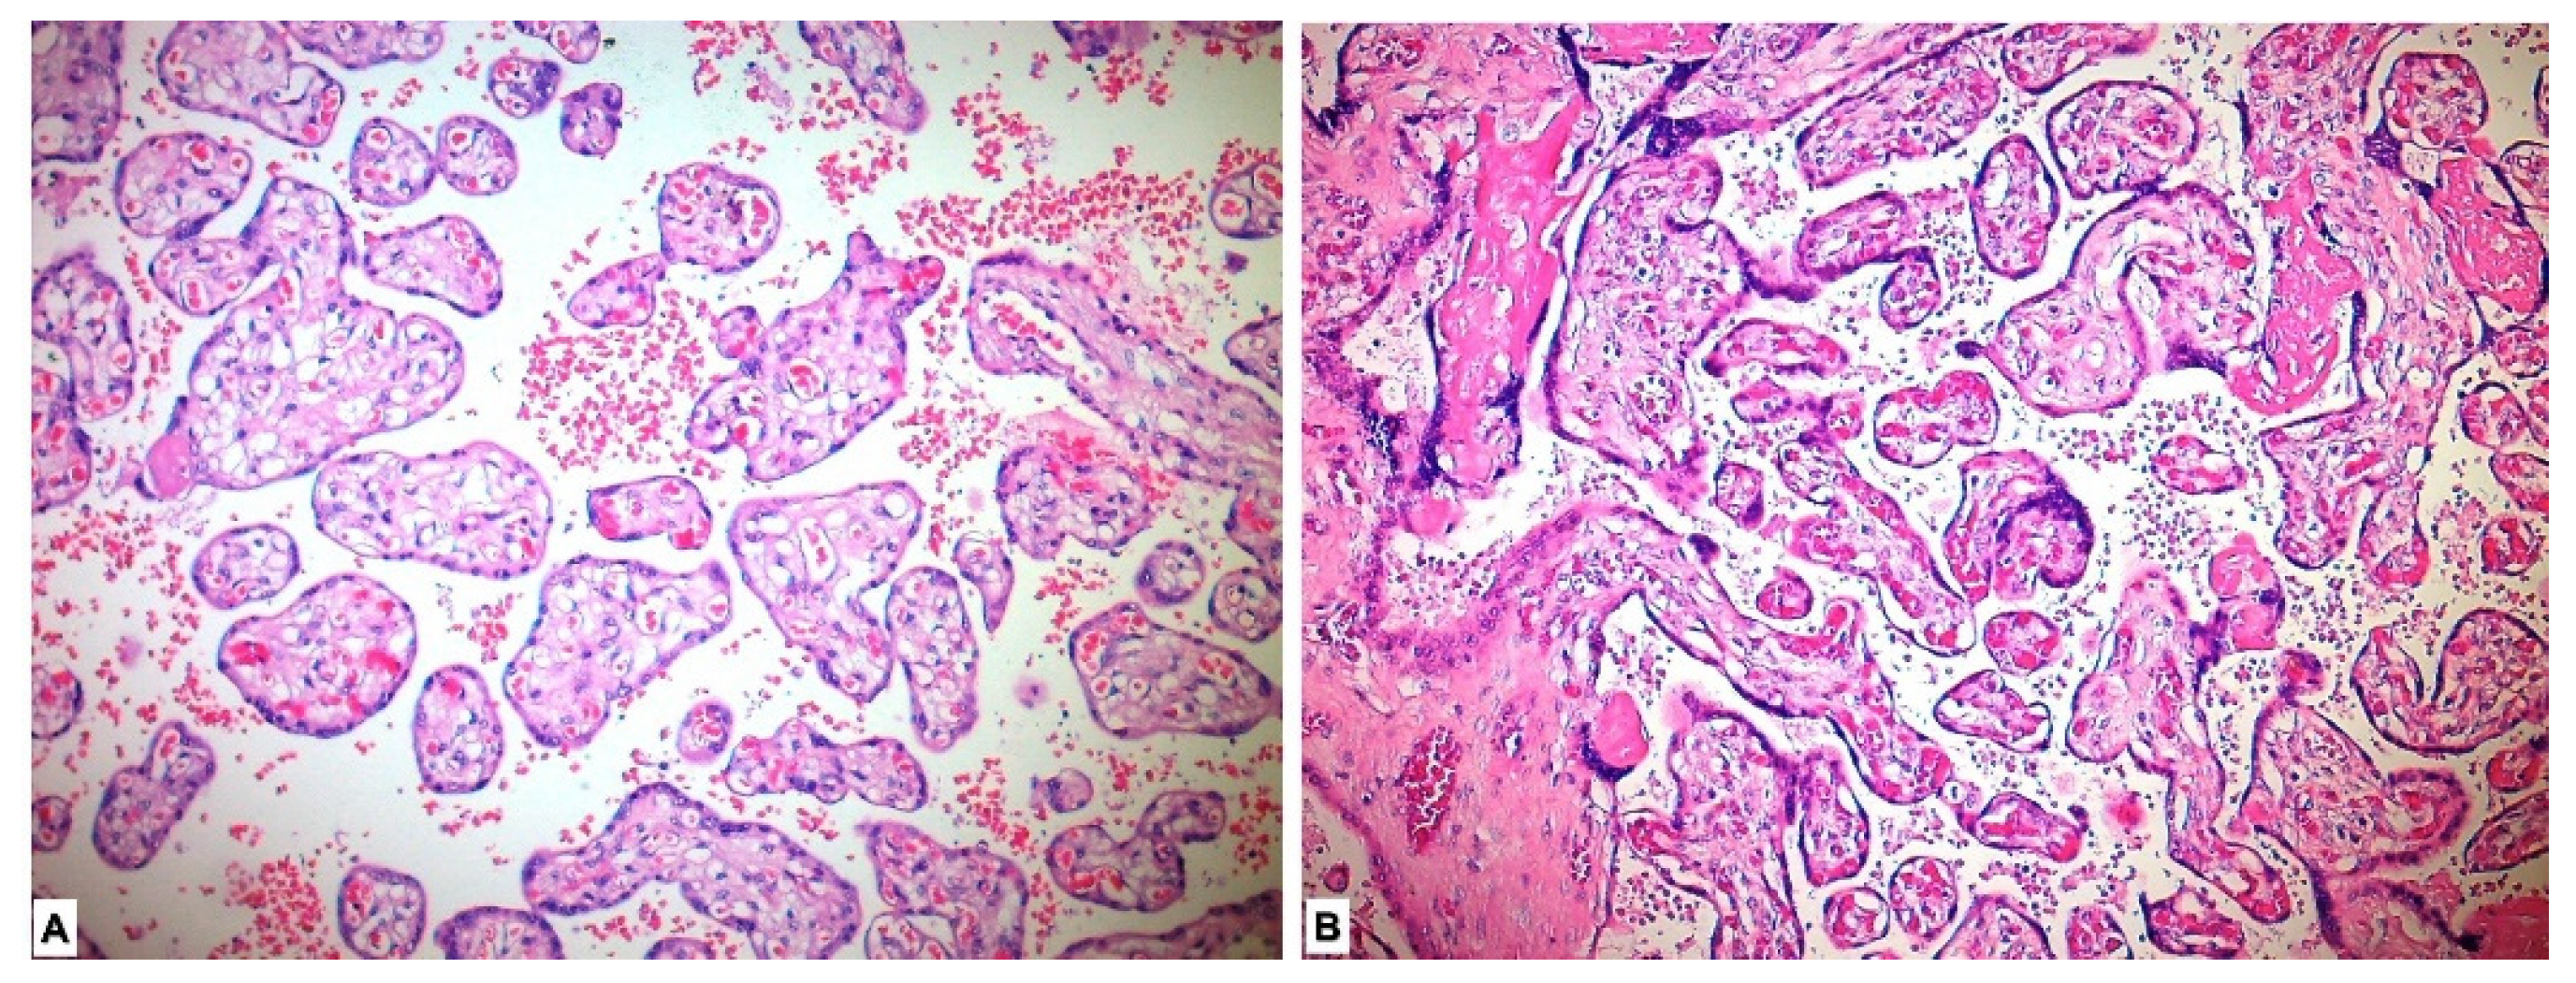

3.2. Histopathological Results

3.3. Immunohistochemical Results